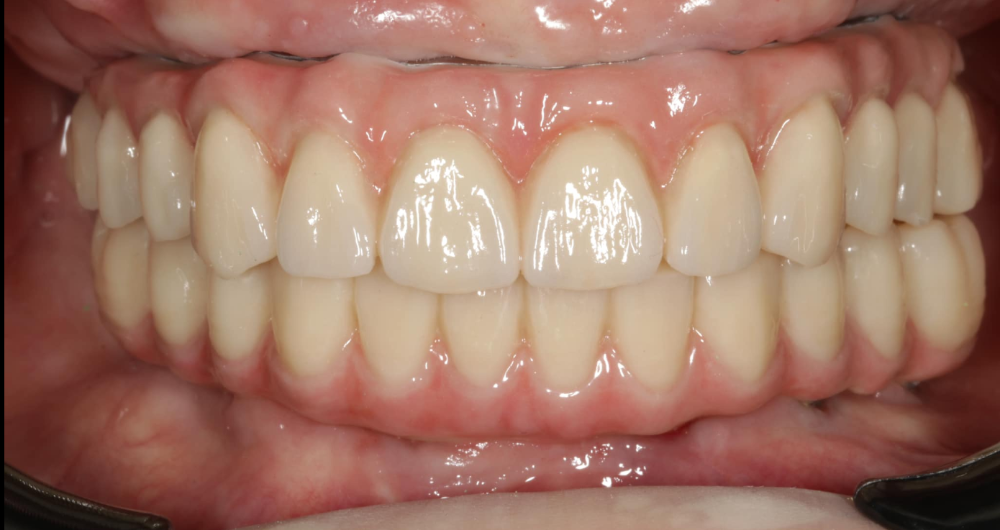

Používáme multivrstvý zirkon pro maximální estetiku, pevnost a dlouhou životnost.

Technika All-on-X — II. fáze

Ukázky práce před a po